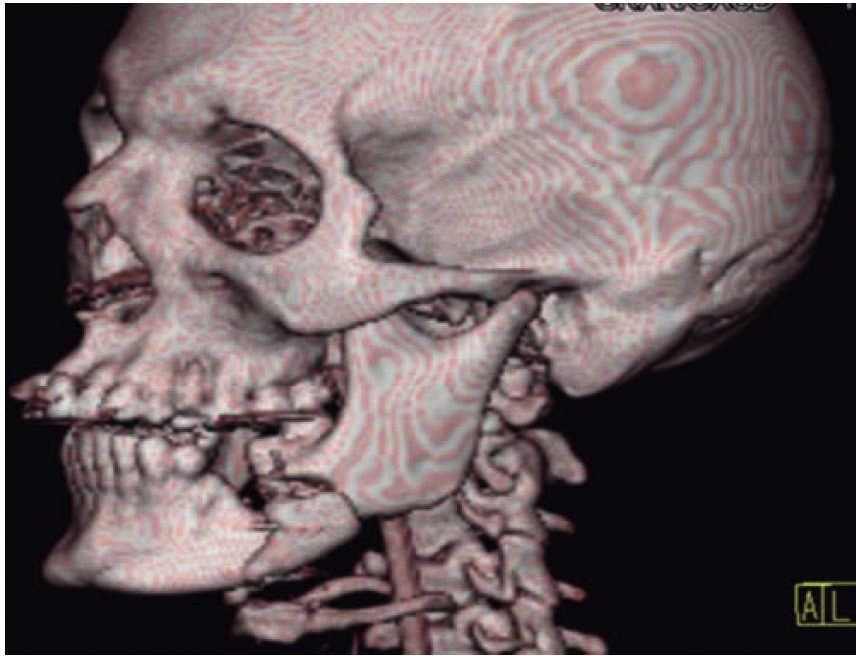

Femenino de 73 años con diagnóstico de fractura de cuerpo mandibular izquierdo por proyectil de arma de fuego (Figura 12). Paciente refiere que es asaltada en la vía pública, le retiran su vehículo y al mostrar resistencia le disparan a dos metros de distancia. Acude a nuestro hospital ocho días posteriores al evento, refiere ingresada previamente en otra casa de salud. A la exploración física presenta zona hiperémica y aumento de volumen en región submandibular izquierda fluctuante. Con orificio de entrada a nivel submandibular izquierdo con presencia de secreción blanca fétida, y orificio de salida a nivel cervical derecho cicatrizado. Intraoralmente edéntula parcial con múltiples focos sépticos en maxilar, en fondo de saco mandibular izquierdo un resto radicular de primer molar en línea de fractura. Movilidad del segmento mandibular importante por fractura de cuerpo que dificulta la deglución.

Se inicia tratamiento terapéutico de inmunización, antibioticoterapia, analgesia, extracción de focos sépticos y lavados mecánicos de la herida. La paciente no cuenta con prótesis ni parcial ni removible por lo que para establecer la relación intermaxilar y altura facial se confeccionan férulas de Gunning (Figura 13). A los diez días del tratamiento inicial se encuentra con adecuada cicatrización a nivel alveolar, con presencia de secreción no fétida a nivel de herida mandibular y se procede a realizar el segundo procedimiento mediante un abordaje extraoral con una placa de reconstrucción mandibular 2.4 y una placa 2.0 para un segmento óseo (Figuras 14 y 15). Se otorga el alta, acude a valoraciones periódicas con buena cicatrización (Figura 16), y adecuada movilidad mandibular. A las tres semanas posteriores a la reconstrucción se indica a la paciente iniciar tratamiento protésico para su rehabilitación.